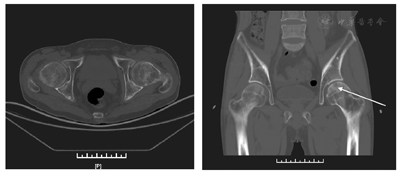

病例1,男,48岁,逐渐出现左踝关节、左下肢、左髋部疼痛2年后,来疼痛科就诊。疼痛以左侧髋关节处疼痛为主,为活动痛,呈持续性痛,VAS>7,有跛行,左髋叩痛(+),左下肢4字试验(+),骨盆X线片发现左髂骨、左股骨局部骨密度明显降低。骨盆CT未见异常,髋关节CT显示左股骨头及双侧股骨近端骨质密度不均匀,见图1。肿瘤全套检查显示甲胎蛋白13.32 ng/ml,余均正常。碱性磷酸酶317 U/L(正常值为15~112 U/L),尿酸125 μmol/L(男性正常值为210~430 μmol/L),磷0.46 mmol/L(正常值为0.80~1.60 mmol/L),尿素8.2 mmol/L(正常值为2.5~6.4 mmol/L),尿蛋白++++,尿隐血+++。骨髓瘤血液学检测(-),ECT显示:全身多发肋骨、关节骨代谢活跃,见图2。结合SPECT/CT及血磷明显降低,考虑低磷软骨症可能性大。追问既往史,患者有慢性乙型肝炎,服用阿德福韦酯10 mg,1次/d,5年,结合患者低尿酸、高碱性磷酸酶等异常,考虑为阿德福韦酯所致低血磷性骨软化症[1,2],并引起下腰痛。遂嘱患者停用阿德福韦酯,用口服拉米夫定(lamivu-dine)代替,并口服骨化三醇(calcitriol)和碳酸钙D3,促进钙,磷的吸收。疼痛逐渐好转,3个月后,疼痛完全消失,下肢活动恢复正常,血磷,尿酸等各项指标均在正常范围内,见表1。